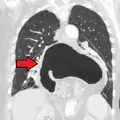

Four types of esophageal hiatal hernia are identified:[8]

Type I: A type I hernia, also known as a sliding hiatal hernia, occurs when part of the stomach slides up through the hiatal opening in the diaphragm.[9] There is a widening of the muscular hiatal tunnel and circumferential laxity of the phrenoesophageal ligament, allowing a portion of the gastric cardia to herniate upward into the posterior mediastinum. The clinical significance of type I hernias is in their association with reflux disease. Sliding hernias are the most common type and account for 95% of all hiatal hernias.[10] (C)

Type II: A type II hernia, also known as a paraesophageal or rolling hernia, occurs when the fundus and greater curvature of the stomach roll up through the diaphragm, forming a pocket alongside the esophagus.[9] It results from a localized defect in the phrenoesophageal ligament while the gastroesophageal junction remains fixed to the pre aortic fascia and the median arcuate ligament. The gastric fundus then serves as the leading point of herniation. Although type II hernias are associated with reflux disease, their primary clinical significance lies in the potential for mechanical complications. (D)

Type III: Type III hernias have elements of both types I and II hernias. With progressive enlargement of the hernia through the hiatus, the phrenoesophageal ligament stretches, displacing the gastroesophageal junction above the diaphragm, thereby adding a sliding element to the type II hernia.

Type IV: Type IV hiatus hernia is associated with a large defect in the phrenoesophageal ligament, allowing other organs, such as colon, spleen, pancreas and small intestine to enter the hernia sac.

The end stage of type I and type II hernias occurs when the whole stomach migrates up into the chest by rotating 180° around its longitudinal axis, with the cardia and pylorus as fixed points. In this situation the abnormality is usually referred to as an intrathoracic stomach.